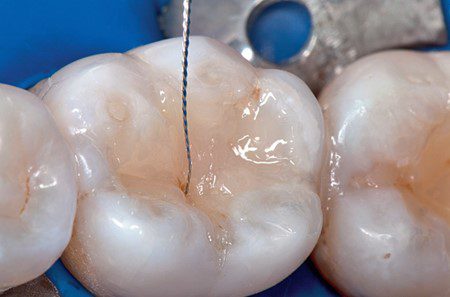

Hình 6. Để tạo màu hố rãnh mặt nhại, sử dụng một lượng nhỏ màu đất son pha loãng (Kolor + Plus, Kerr) và đặt bằng trâm nội nha số 08 (K-File, SybronEndo) vào vùng lõm cuối cùng chưa được trùng hợp và trùng hợp trong 40 giây.